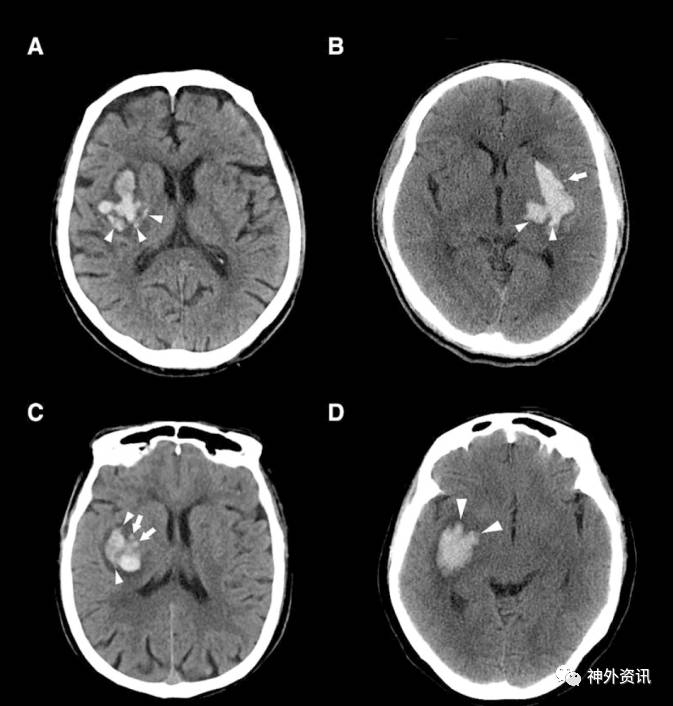

作者纳入2011年7月至2016年9月间收治的252例ICH患者。纳入标准:①年龄>18岁;②发病6小时内首次CT平扫;③首次CT后30小时内复查CT。排除标准:①在CT复查前行手术治疗的患者;②出血继发于脑动静脉畸形、外伤、颅内动脉瘤、脑肿瘤以及脑梗死性出血等;③凝血功能障碍相关性脑出血。CT平扫“岛征”定义为:≥3处散在的、均与主要血肿分离的小血肿;或≥4处小血肿,其中几个可以与主要血肿相连(图1、2)。血肿体积增加大于基础血肿量的33%或>6ml则定义为血肿扩大。患者第90天进行mRS评分,mRS评分≥3分为预后不良。通过多因素logistic回归分析CT平扫“岛征”与患者早期血肿扩大和预后的关系。

图1. CT平扫“岛征”图示说明。A.1例基底节区脑出血患者,箭头所指为3处散在的小血肿,均与主要血肿不相连;B.1例壳核出血患者,三角形所指为3处散在、与主要血肿分离的小血肿,3处小血肿与主要血肿之间存在低密度影;C.1例脑叶出血患者,三角形所指为4处散在、与主要血肿分离的小血肿;D.1例基底节区大量脑出血并破入脑室的患者,三角形所指为4处与主要血肿相连的气泡状或发芽状的小血肿,箭头所指为1处散在、与主要血肿分离的小血肿。